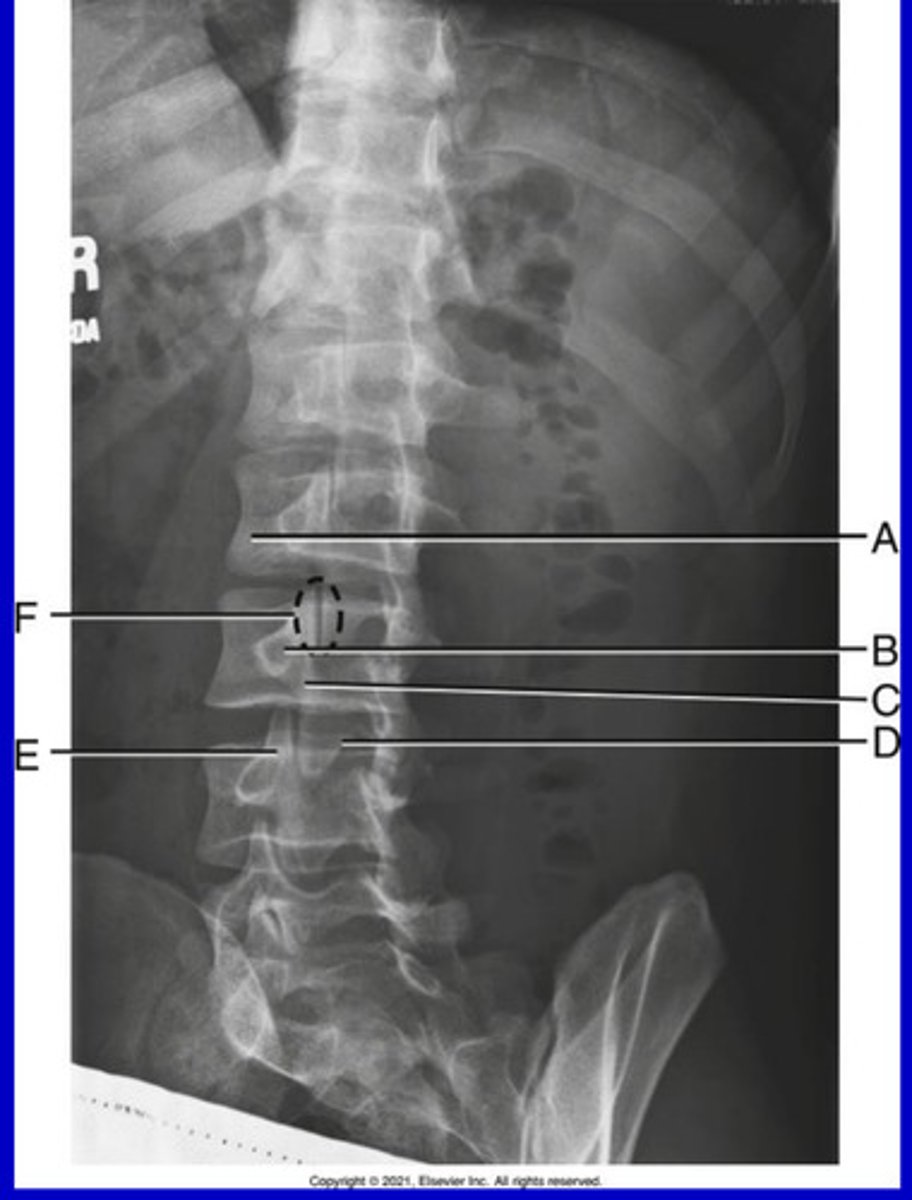

R sacroiliac joint

A.

L1 transverse process

B.

L2 spinous process

C.

L3-4 intervertebral space

D.

Ala of sacrum

E.

AP L spine

What position?